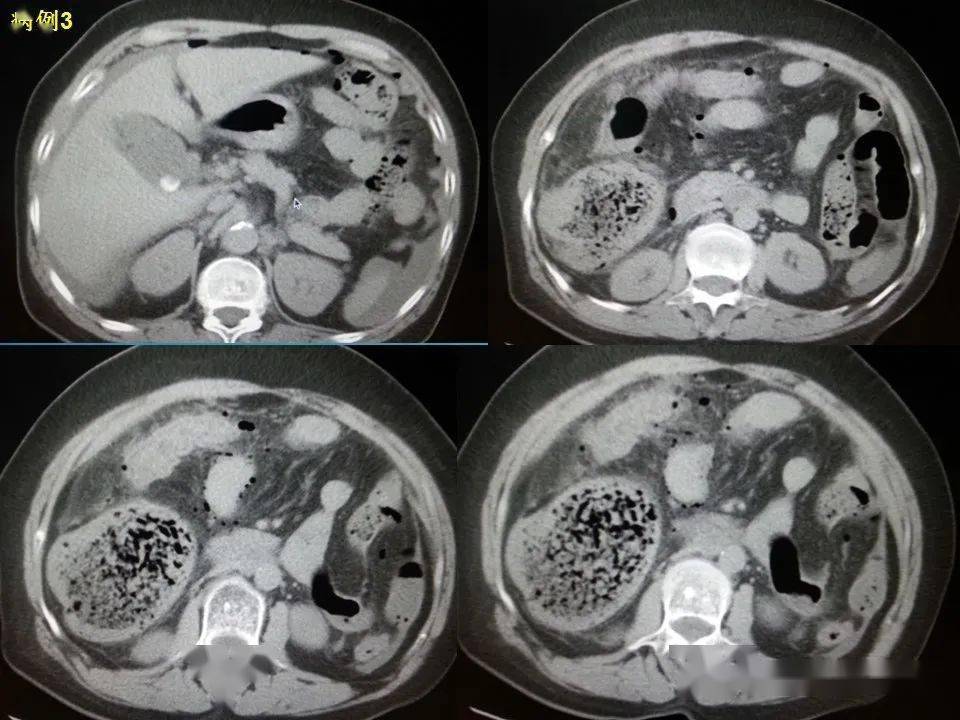

新余市人民医院有段小肠壁明显水肿,旁边有渗出,早期肠穿孔没有游离

图片尺寸1080x1920